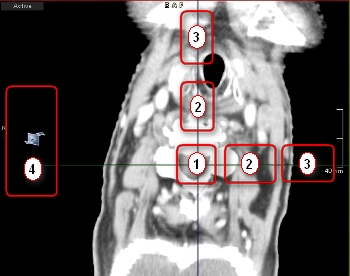

Η προεπιλεγμένη διάταξη MPR αποτελείται από τρία χρωματικά κωδικοποιημένα παράθυρα που εμφανίζουν εγκάρσια, στεφανιαία και οβελιαία επίπεδα. Κάθε ένα από αυτά τα παράθυρα περιέχει δύο τεμνόμενες γραμμές εντοπισμού που αντιπροσωπεύουν τα επίπεδα που είναι ορατά στα δύο άλλα παράθυρα. Οι γραμμές εντοπισμού είναι επίσης χρωματικά κωδικοποιημένες για να αντιστοιχούν στις προβολές που αντιπροσωπεύουν.

![]() | Μετατόπιση κέντρου (1) | Μετακινήστε τη θέση δύο επιπέδων ταυτόχρονα σύροντας τη λαβή μετατόπισης κέντρου. |

![]() | Μετατόπιση επιπέδου (2) | Μετακινήστε τη θέση ενός επιπέδου σύροντας τη λαβή μετατόπισης επιπέδου. |

![]() | Περιστροφή επιπέδου (3) | Περιστρέψτε το επίπεδο (το ορθογώνιο επίπεδο επιστρέφεται επίσης) σύροντας τη λαβή περιστροφής επιπέδου. |

![]() | Λεπτομερής πλοήγηση (4) | Περιηγηθείτε στον όγκο που έχει υποστεί ανασύνθεση σύροντας την περιοχή ενδιαφέροντος λεπτομερούς πλοήγησης. |